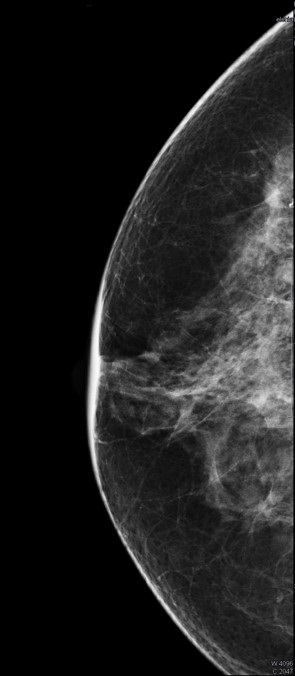

Al tratarse de una mujer de 66 años y que además, no está embarazada, la prueba de elección para buscar patología mamaria es la mamografía, pues es una técnica que utiliza una dosis mínima de radiación y que nos permite una visión completa de toda la mama. Además, nos permite detectar lesiones no detectables con otras técnicas, o incluso a la palpación, por lo que en la actualidad es la estándar de referencia por su mejor relación beneficio/riesgo.

En la mamografía de la mama derecha, de la cual teníamos sospecha de patología, observamos unas microcalcificaciones redondeadas, con centro radiotransparente, que son benignas. No obstante, en la mama izquierda (imágenes adjuntas, siendo la izquierda oblicua y la derecha cráneo-caudal) encontramos un hallazgo que había pasado desapercibido en el centro de salud.